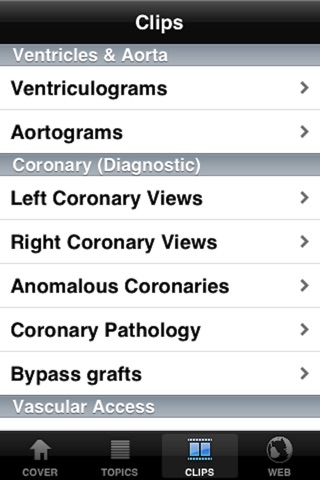

CathLab App provides easy to access information for education in the setting of cardiac catheterization laboratory. The information elements include description of different procedural basics as well as illustrations. In addition video clips inside the app and from world wide web supplement the content in a meaningful way.